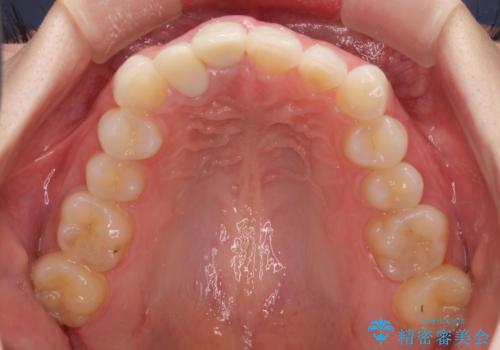

- 一度矯正治療を希望して始めたものの断念し、前歯をセラミッククラウンで治療した後に、やはり矯正でしっかり治したいとのことで来院された患者様です。

当初、前歯の歯列矯正を希望して銀座院に来院され、補助装置を装着するところまで進んだのですが断念してしまいました。

その後、他院で気になる前歯をセラミッククラウンで補綴治療をしたそうですが、やはり歯列を整えたいとのことで再度来院されました。

クラウンの状態は、根管治療の状態も含めて決して良い状態とは言えず、矯正治療後の根管治療と補綴治療の再治療を前提として、インビザラインによる矯正治療を行うこととしました。

治療前、下顎前歯はほとんど見えない咬み合わせでしたが、矯正治療によりディープバイトが改善されました。

矯正治療中に前歯2本のクラウンは外れてしまい、途中仮歯に替える必要があったので期間は掛かりましたが、歯列も整い、負担のかからない咬み合わせを達成することができました。